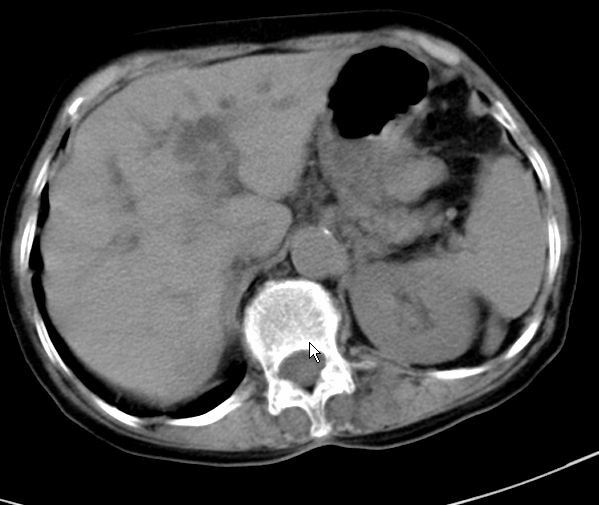

以下是引用zjzjr在2008-12-16 12:49:00的发言:[br]肝内外胆管全程扩张,胆囊明显增大,未见占位征像.建议mrcp.

以下是引用jiangjing在2008-12-16 13:19:00的发言:[br]肝内外胆管全程扩张,胆囊明显增大,扩张胆总管下段径较中上段小,未见胰管扩张,提示胆总管远端梗阻伴感染.建议增强及mrcp 检查

以下是引用朱亮在2008-12-16 12:54:00的发言:[br]胆总管远端应薄层扫描 胆总管逐渐变细 考虑胆系慢性炎症